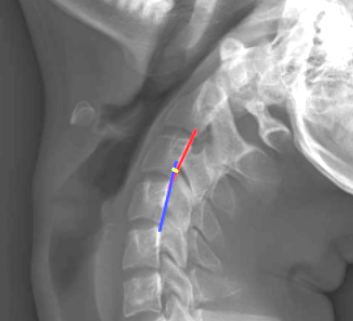

Image Type Cervical Spine X-Ray CT Scan MRI Scan Atlantodental Interval (ADI) Basion-Axial Interval Basion-Dens Interval (BDI) C2 Tilt C2–C7 Coronal Cobb Angle Cervical C2-7 lordosis C2-C7 Translation Chamberlain’s Line / McGregor’s Line Flexion-Extension George’s Line (Posterior Cervical Line) K-Line Interpedicular Distance (IPD) Occiput-C2 Angle Occipital Condyle–C1 Interval (CCI) Posterior Atlantodental Interval (PADI) Power’s ratio Sagittal Canal Diameter Sagittal Vertical Axis (SVA) Spinolaminar line Swischuk Line T1 Slope Torg/Pavlov Canal-to-Body Ratio